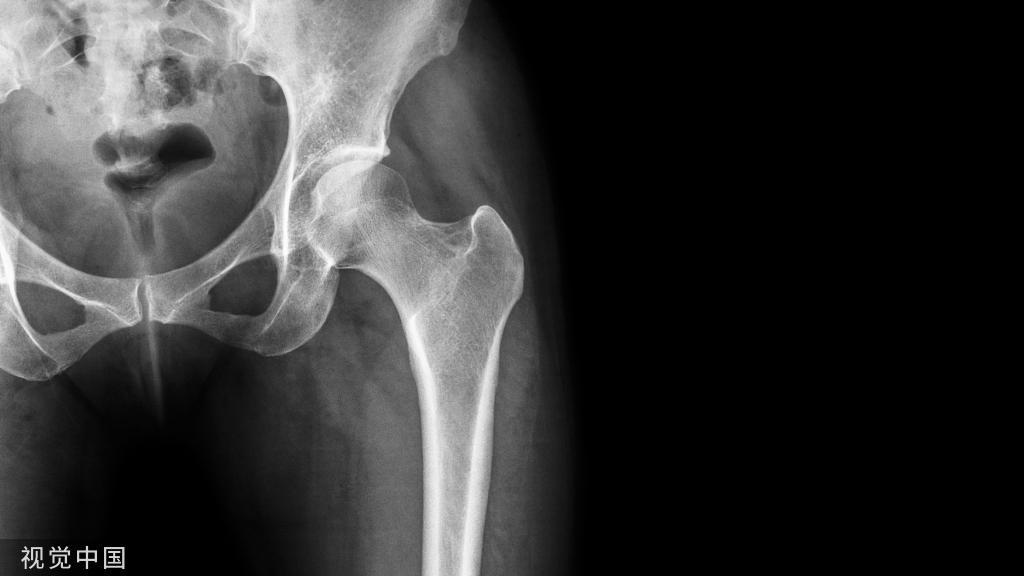

病例:男性,14岁。

胫骨近端骨骺似乎见撕裂骨折?